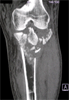

Follow

Up

X-Ray after frame removal and union

good return of knee motion soon after frame removal